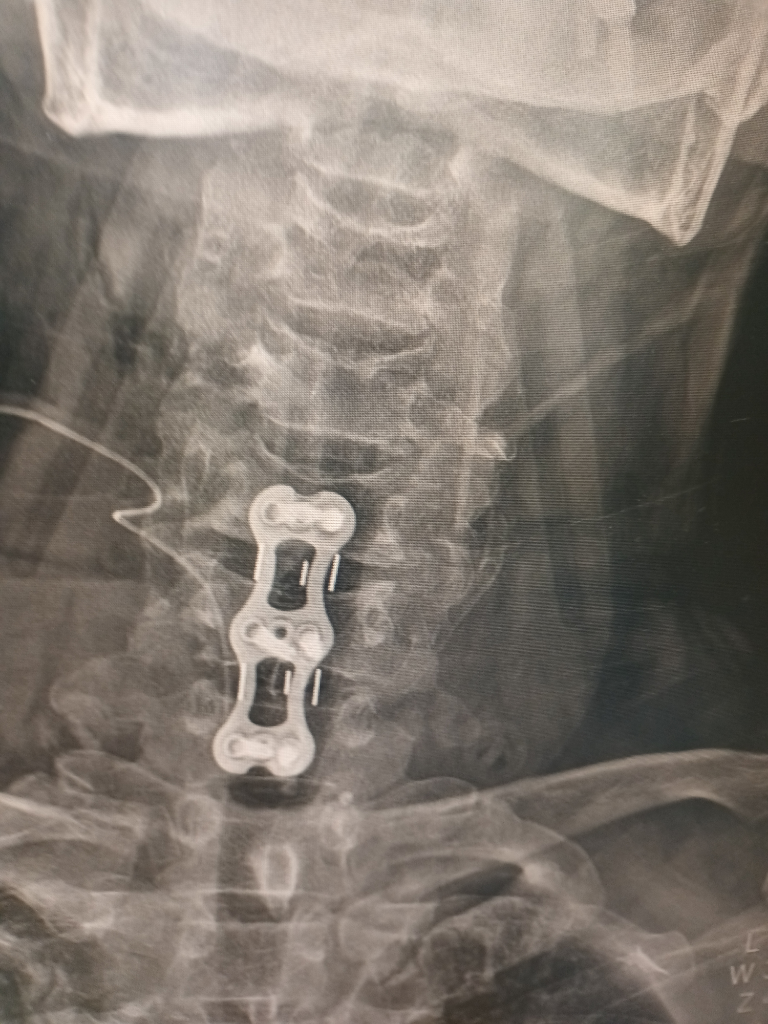

비보호 좌회전에서 파란불에 직진중 상대방차가 과속해서 사고가 났구요 119타고가서 병원에 입원했는데 목보호대만 하고 있는데 4일이 지나도 팔도 안올라가고 상태가 안좋아 mri찍었는데 갑자기 큰병원가서 정밀검사받으라고 그병원 앰블런스로 대학병원 응급실로 왔구요 바로 입원하고 수술하자고.경추6.7번골절 경추5번이 신경을 눌러서 팔이 안올라가는거라고 하네요 다음날 수술하고 잘됐다고 3개월은 지나야 좋아진다고 하는데 수술끝나고 퇴원하라고 하네요 수술한 당사자는 계속 등이랑 팔 가슴쪽 통증을 호소하네요 매일 진통제약이랑 주사 맞고 있는데 약기운 떨어지면 많이 아파해요 ~집가까운정형외과로 가야할거 같은데 아직 정확한 진단주수도 모르고 재활하고 언제쯤 합의해야 하는지 어느 정도 입원해야 하는지 후유장해진단도 받는건지 합의금은 어느정도인지 전혀 모르겠어요 자세한 말씀 부탁드려요

상해정도는 경추골절로 유합술을 시행한 상황으로 충분한 재활 치료를 한후 그에 따른 후유장해진단을 받아야 합니다.